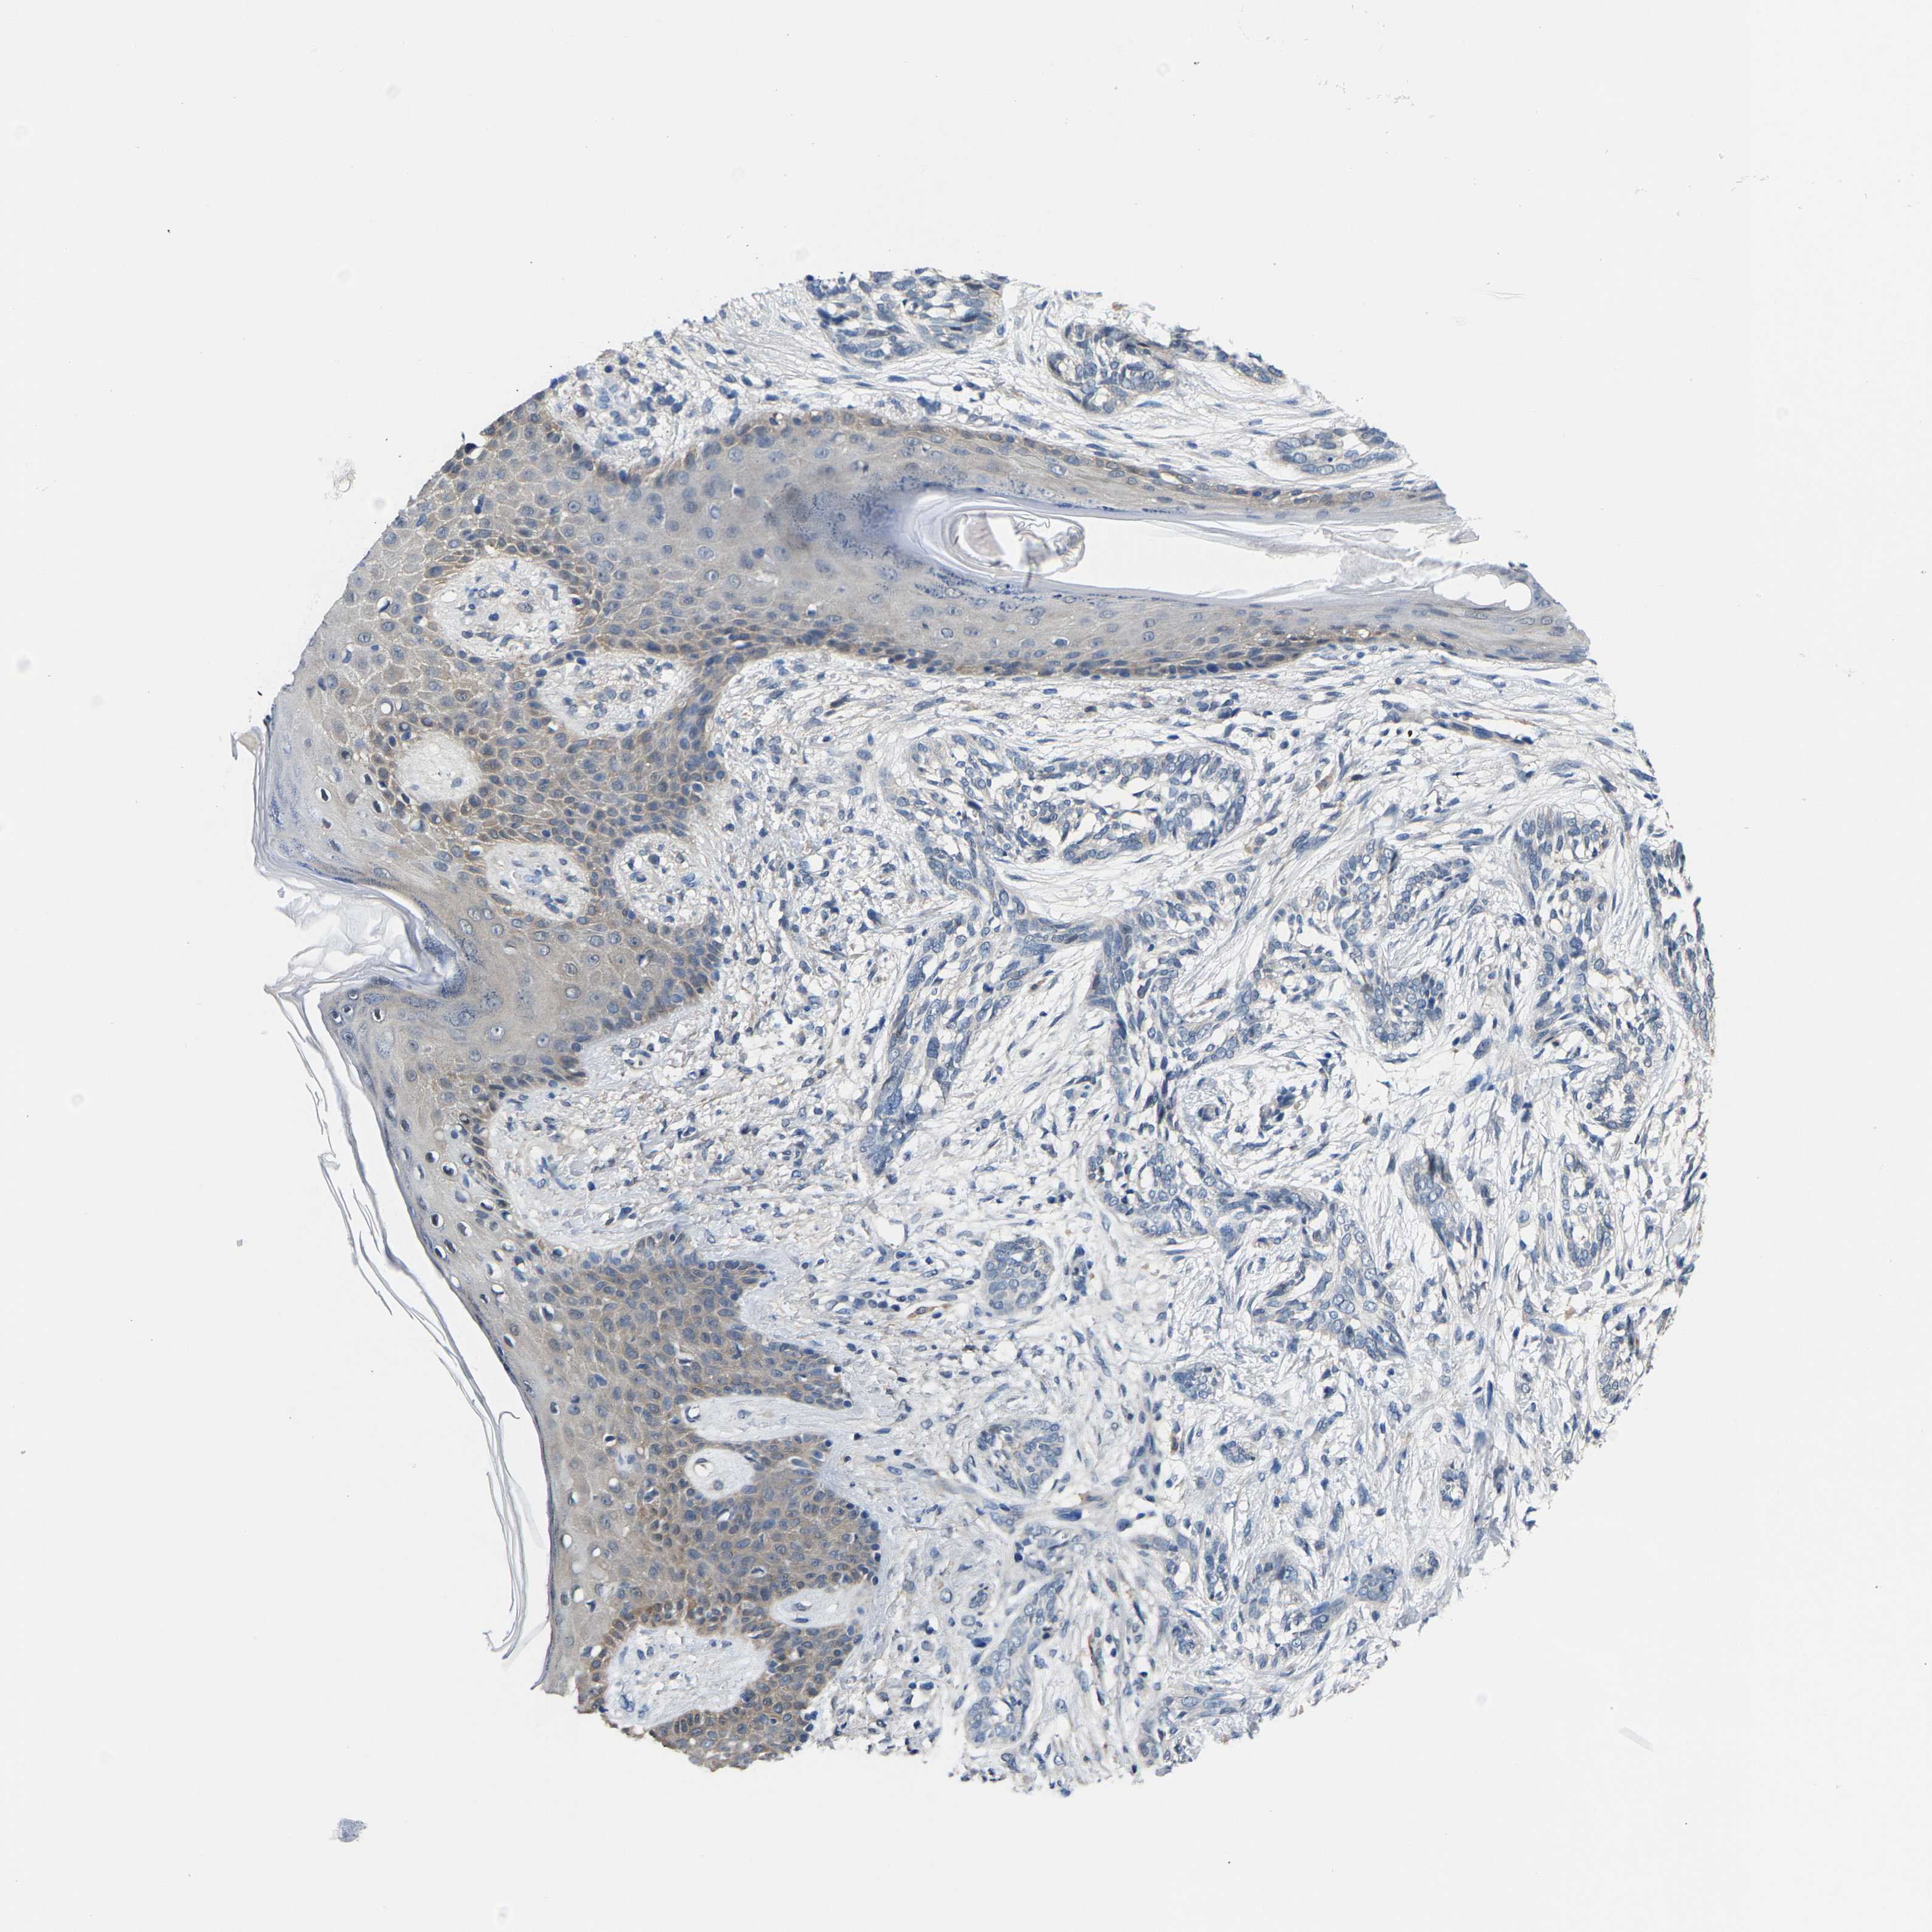

SKIN CANCER - Protein expressioni

A mouse-over function shows sample information and annotation data. Click on an image to view it in a full screen mode. Samples can be filtered based on level of antibody staining by selecting one or several of the following categories: high, medium, low and not detected. The assay and annotation is described here.

Each image is clickable and will lead to virtual microscopy that enables deeper exploration of all samples and also displays staining intensity scores, fraction scores and subcellular localization as well as patient and tissue information for each sample.

Antibody HPA019957

Staining

High

Medium

Low

Not detected

Intensity

Strong

Moderate

Weak

Negative

Quantity

>75%

75%-25%

<25%

None

Location

Nuclear

Cytoplasmic/membranous

Cytoplasmic/membranous,nuclear

Squamous cell carcinoma in situ, NOS

Squamous cell carcinoma, NOS

Squamous cell carcinoma, metastatic, NOS

Basal cell carcinoma